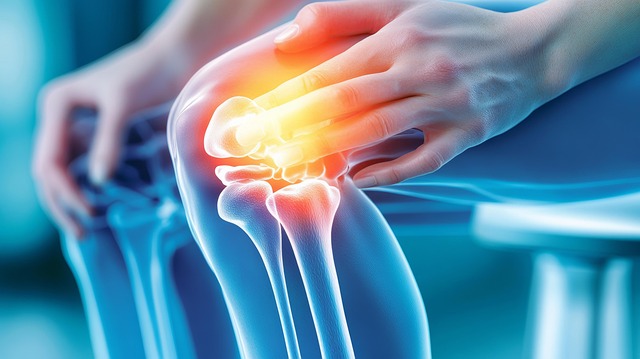

3. 질환별 고관절 증상 비교표

| 고관절 점액낭염 | 엉덩이 옆쪽 | 눌렀을 때 통증 증가 |

| FAI 충돌증후군 | 사타구니 | 굽힘·내회전 시 찝힘 |

| Labrum 파열 | 사타구니, 소리 | 젊은 층 많음 |

| 퇴행성 고관절염 | 전반적 | 아침 뻣뻣함, 보행 통증 |

| 외측 통증 증후군 | 허리~엉덩이 | 코어 약화 관련 |